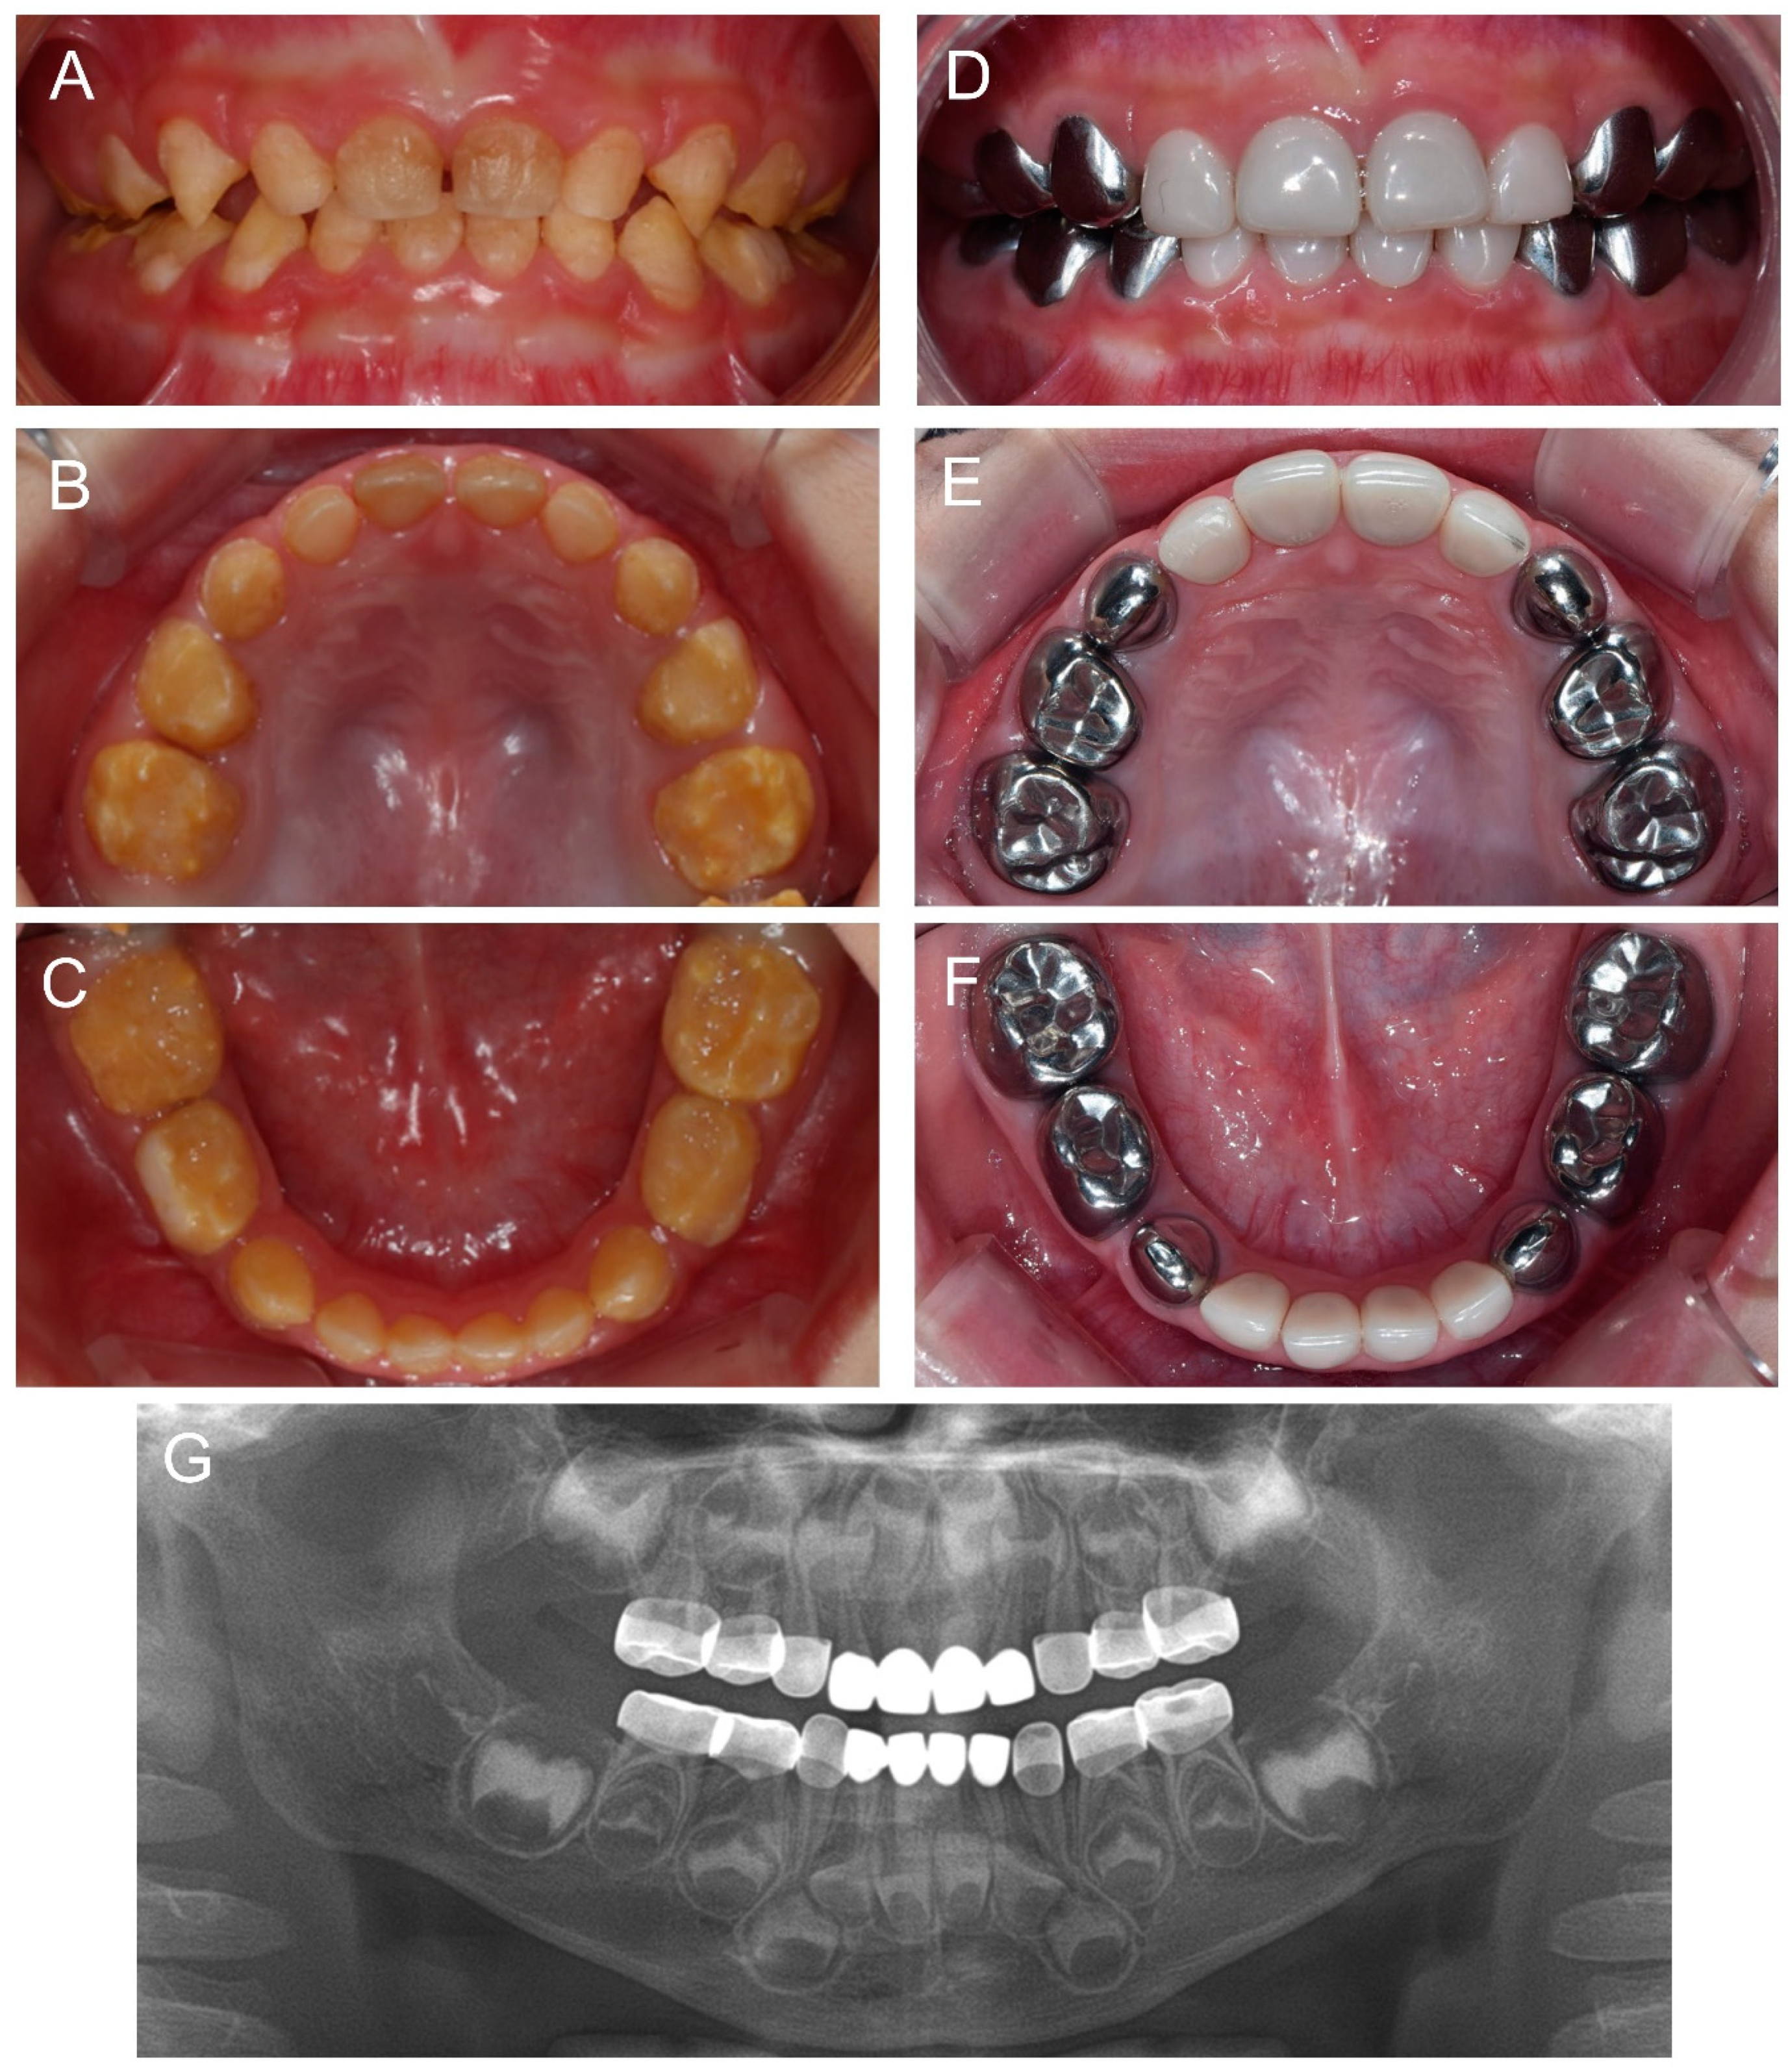

About 10 months after the first visit of the proband, a cousin of the proband presented for the management of the affected dentition at age 2Y. Oral hygiene instruction was given, and the same preventive measure was recommended. Completion of deciduous dentition was observed at the six-month follow-up, and discomfort in the mandibular posterior area was reported a month later. Full-mouth restoration was performed under outpatient GA at age 2Y11M. The deciduous mandibular anterior teeth were treated with celluloid resin crowns, because there was not enough interdental space for zirconia crowns (Figure 4).

Figure 4.

Clinical photos and panoramic radiograph of the affected individual (IV:1). (A–C) Clinical photos of the proband before the treatment at age 2 years 11 months. (D–F) Clinical photos of the proband after the treatment. The deciduous molars were treated with stainless steel crowns, and the deciduous canines and maxillary anterior teeth were treated with zirconia crowns. The deciduous mandibular anterior teeth were treated with celluloid resin crowns. (G) Panoramic radiograph at age 4 years 9 months.